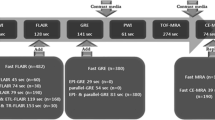

Imaging protocols

All patients underwent both brain CT angiography (SOMATOM Definition AS+, Siemens Healthcare, Forchheim, Germany) and brain 3-T MRI (Discovery MR750; GE Healthcare, Milwaukee, USA). The brain CT angiography protocol included 1-mm non-contrast CT and CT angiography with the same thickness. The maximum intensity projection using source data was obtained. Our stroke MR imaging protocol for acute stroke included DWI and T2-FLAIR. In addition, dynamic susceptibility contrast (DSC) perfusion-weighted imaging and 3D T1W BB FSE were acquired sequentially after administration of a compact bolus (0.1 mmol/kg) of gadobutrol at an injection rate of 5 mL/s. The parameters for DWI were repetition time (TR)/echo time (TE) = 8000/65.6 ms; slice thickness = 3mm; gap = 0.1 mm; matrix size = 160 × 160; field of view (FOV) = 240 × 240 mm2; three directions; b value = 0 and 1000 s/mm2. T2-FLAIR images were acquired with the following parameters: TR/TE = 12,000/140 ms; inversion time (TI) = 2500 ms; slice thickness = 4 mm; gap = 1 mm; flip angle = 110°; FOV = 210 × 210 mm2; matrix = 352 × 353; and 30 contiguous sections for a total acquisition of 3 min 20 s. DSC perfusion MRI employed gradient echo-planar imaging and imaging parameters were TR/TE =1500/23 ms; slice thickness = 4 mm; gap = 1 mm; flip angle = 60°; FOV = 220 × 220 mm2; matrix = 100 × 100. The acquisition time was 1 min 40 s. To obtain 3D T1W BB FSE, motion-sensitised driven equilibrium prepared pulse was added in the front of 3D T1W FSE with variable flip angle. The scan parameters of 3D T1W FSE with variable flip angle were TR/TE = 500/24.5 ms; slice thickness = 1 mm; echo train length = 24; flip angle = variable; FOV = 220 × 220 mm2; matrix = 256 × 224; 170 axial slices. The acquisition time was 4 min 50 s.

The contrast-to-noise ratio between the hyperintense artery and adjacent grey matter on Gd-enhanced 3D T1W BB FSE was significantly higher than that on T2-FLAIR (2.27 ± 1.65 versus 0.94 ± 0.86, p = 0.01, Fig. 2).

Overall, agreement of hyperintense arteries on T2-FLAIR and Gd-enhanced 3D T1W BB FSE was excellent (ρ = 0.76, p < 0.01, Fig. 3). Regarding each ASPECT territory, agreements were excellent in I, M1, M2, M3 and M4 (ρ = 0.87, 0.8, 0.78, 0.81 and 0.79 respectively, p < 0.01), good in M5 (ρ = 0.67, p = 0.01) and fair in M6 (ρ = 0.56, p = 0.04) (Table 2).